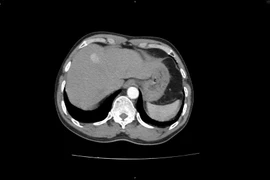

Can thiệp TIPS cứu bệnh nhân xơ gan nặng do rượu

Bệnh nhân 46 tuổi, xơ gan do rượu, nhiều lần xuất huyết tiêu hóa do giãn tĩnh mạch thực quản và phình vị vừa được các bác sĩ can thiệp TIPS thành công.